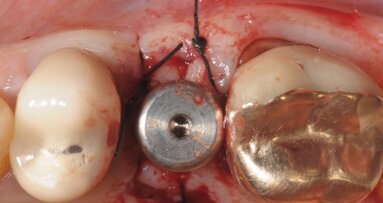

L’utilizzo di un impianto in ceramica prevede le stesse procedure chirurgiche usate per gli impianti convenzionali in titanio, nello specifico impiego di impianti Monotype, cioè a corpo unico col moncone, esistono degli analoghi chirurgici che determinano l’altezza del moncone che si vuole adottare. Nel caso specifico la procedura chirurgica si è basa sulla diagnosi radiografica endorale e sulla visione clinica dell’alveolo successiva all’estrazione, cercando di posizionare l’impianto nella parte mesio-palatale dell’alveolo e cerando di impattare l’apice dell’impianto nella porzione ossea sovrastante l’apice radicolare. Ovviamente la posizione deve anche tener conto di un’adeguata inclinazione rispetto alla futura corona protesica, alla distanza inter-arcata con la porzione apicale del moncone e al rispetto delle papille limitrofe (Fig. 4). A preparazione impostata andiamo a scegliere tra 2 diverse altezze di moncone (4 mm o 5.5 mm) (Fig. 5). L’impianto è custodito in un’apposito sostegno sagomato in cui si trova anche il mounter utilizzabile per un’inserimento manuale o a manipolo (Fig. 6). Sul mounter è disegnata una linea con 3 punti verticali che identificano ciascuna delle 4 facce piane del moncone implantare e la distanza tra loro consente di stabilire nella fase di posizionamento la profondità a cui si pone l’impianto (Fig. 7). Nel posizionare l’impianto si devono compiere 2 scelte coincidenti, la prima dove collocarsi con la porzione del collocare dell’impianto e conseguentemente quanto approfondire la connessione protesica, mentre la seconda è legata all’altezza del moncone. Nello specifico abbiamo voluto dare una maggior estetica approfondendo una parte del collarino, pur utilizzando un moncone di 5.5 mm che ci garantirà un’ottima stabilità protesica. La rx endorale a fine intervento stabilisce il corretto posizionamento, prima di proseguire con la realizzazione della corona provvisoria.

Avendo scelto inizialmente di voler sostituire anche la corona protesica dell’incisivo controlaterale, al termine del posizionamento implantare abbiamo posizionato un coping di protezione sul moncone che è stato poi utilizzato per collegarlo al provvisorio realizzato (Fig. 9). Il provvisorio è stato realizzato secondo tecnica CAD/CAM nella medesima seduta posizionandolo su entrambi gli elementi. Abbiamo preferito supportare il carico dell’impianto unendo le due corone provvisorie eseguite in telio, allo scopo di garantire maggior resistenza, estetica ma soprattutto per una miglior rifinitura dei margini cervicali. Dopo 3 mesi è stato eseguito nuovo controllo radiografico e clinico rimuovendo il provvisorio. Allo scopo di trasferire all’odontotecnico l’anatomia del tragitto transmucoso è stato aggiunto del composito flou al transfer dedicato all’impronta che nello specifico è solo disponibile nella versione di impronta a strappo (Fig. 11), contemporaneamente abbiamo rilevato anche l’impronta del dente adiacente (Fig. 12). Entrambe le corone sono state realizzate con un core in zirconia sviluppata secondo tecnica CAD/CAM e stratificate in ceramica (Fig. 13). Alla prova delle corone valutiamo gli svincoli occlusali oltre ai movimenti parafunzionali, ricordando che la frattura dell’elemento oggetto di impianto è stato causata durante una funzione masticatoria, indice di un sovraccarico funzionale.

Fig. 9 - Posizionamento di una coppetta in resina come base d’appoggio per la ribasatura del provvisorio.